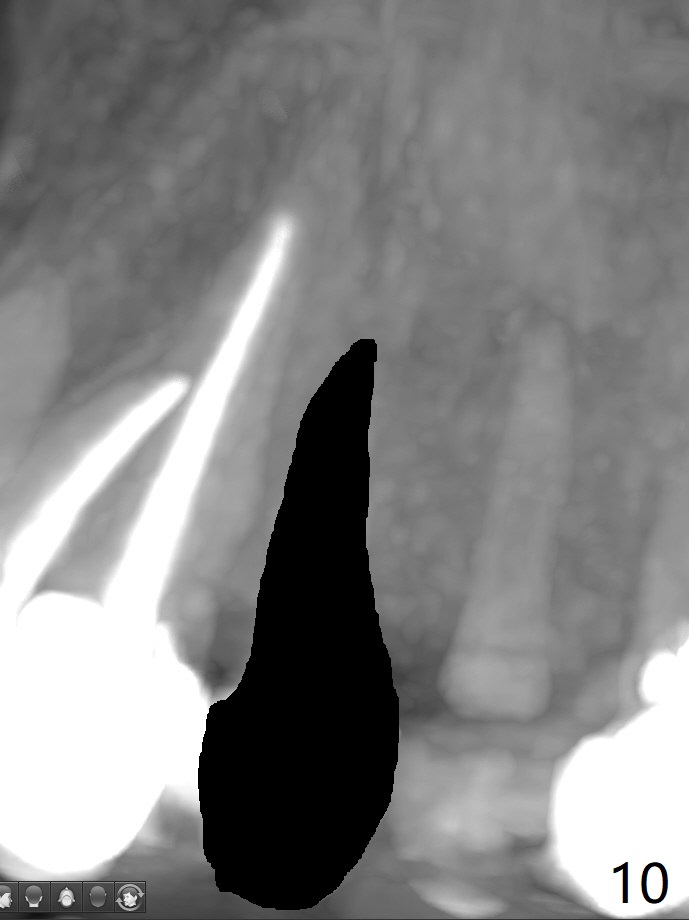

68岁女左上4颊侧瘘道(图一:*),与根尖颊侧骨板缺失相通,其实腭侧根尖周围病变更大(也与颊侧窝相通),术中没有注意腭侧根接近3(图二:P),稀里糊涂的基本顺着腭侧根(颊侧)走向钻洞(图四,与图三理想方向对比),突然记起术前设计钻洞必须在腭侧牙槽窝远中颊侧,在远中建立新洞眼(图五),之后无法再次建立新洞眼,只好利用同一个侧面切割钻头将钻洞往远中移位,同样效果不佳(图六),最后只好放弃,放置粘性骨粉(图七:*),覆盖PRF膜,6个月胶原膜,PGA缝线,牙周胶水。术后重新分析表明顺着腭侧牙槽窝种植与尖牙还是有分离(图八,九:*),因为牙槽窝是斜型的(图十:黑色),不过离颊侧骨板也接近(图八:B)。所以钻洞必须斜型针对远中骨壁,表浅些(图十一:红色箭头);一旦进入骨板,改变角度(图十二:红色箭头),适当矫枉过正,随着植体增大,钻洞会往近中偏移(白色箭头)。最好植体方向理想(图十三)。不过植骨后钻洞偏移可能性比较少。缝线和牙周胶水似乎是一个稳妥固定胶原膜方法。术后病人抱怨水肿严重,术后八天颊侧根尖隆起是由于骨粉推出骨板之外(图十五,十六:*),上颌窦底板无意穿孔(^)伴有上颌窦膜(M)增厚,与术前对比(图十七:上颌窦窦腔清晰)。术后一个月6个月吸收膜不见了,大多数缝线已经脱落,最后两根缝线撤除后,牙槽窝开口已经关闭,好像主要成分是骨粉(图十八)。术后5个月牙槽嵴宽,角化龈也宽,好像可以植入4x11.5毫米植体(图十九)。